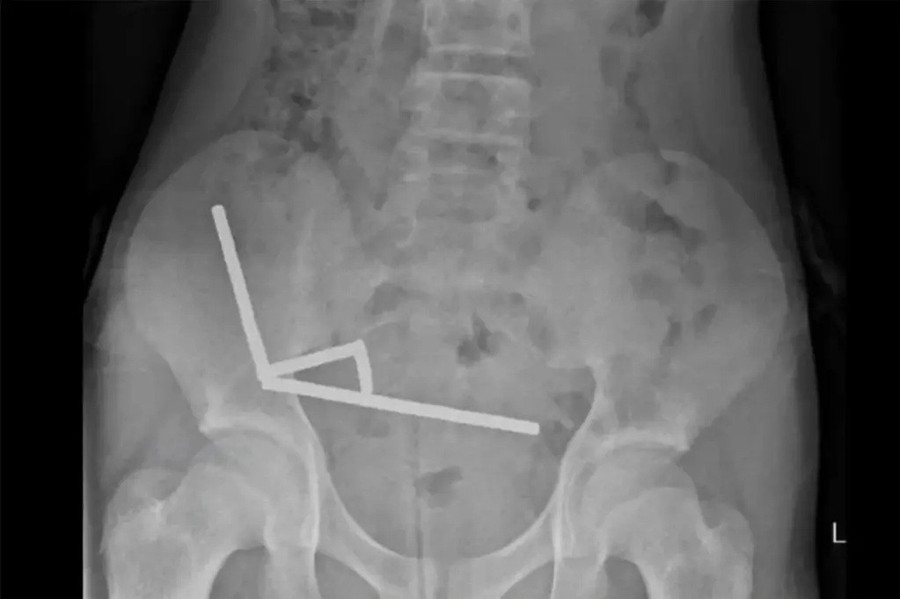

Chụp X-quang cho thấy 4 chuỗi nam châm mắc kẹt ở các đoạn khác nhau của đường tiêu hóa, hút lại với nhau và chặn lưu thông máu tới các mô lân cận. Các bác sĩ cho biết áp lực này gây ra nhiều mảng hoại tử — những vùng niêm mạc ruột bị hoại tử — nên phải phẫu thuật khẩn cấp.